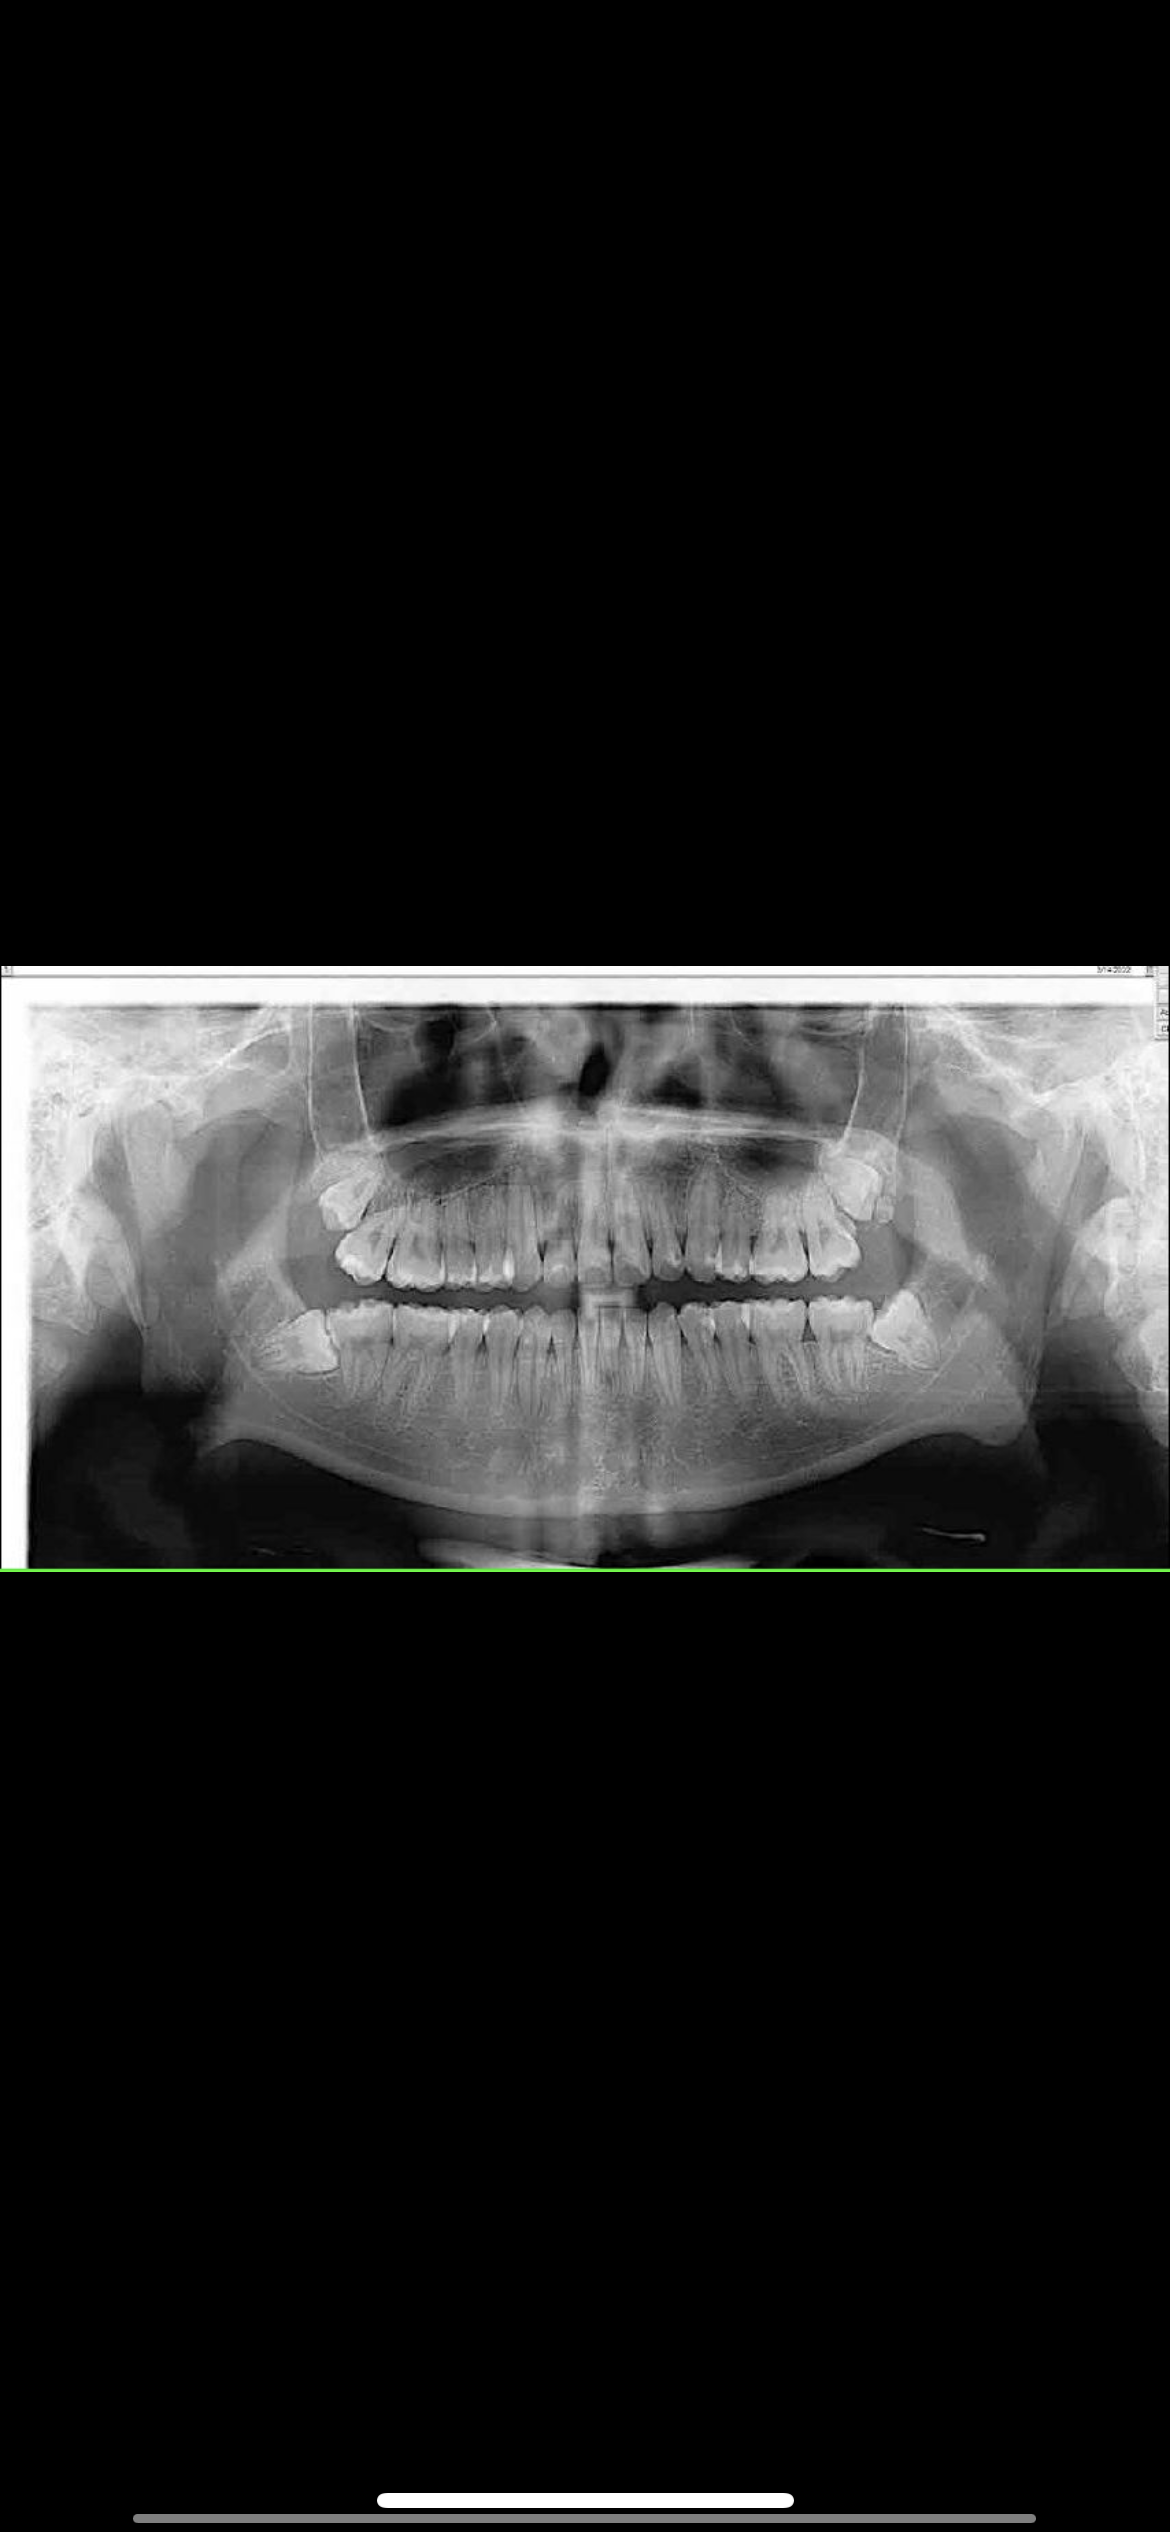

This what they look like

no, you need palate expansion to make room for those teeth

No you shouldn't. Your face will recess bc there isn't any bone supporting it. The 3rd molar is the biggest out of all the teeth and it's nothing short of stupid. You'll lose facial depth, a very attractive thing, and you can develop sleep apnea bc of that.